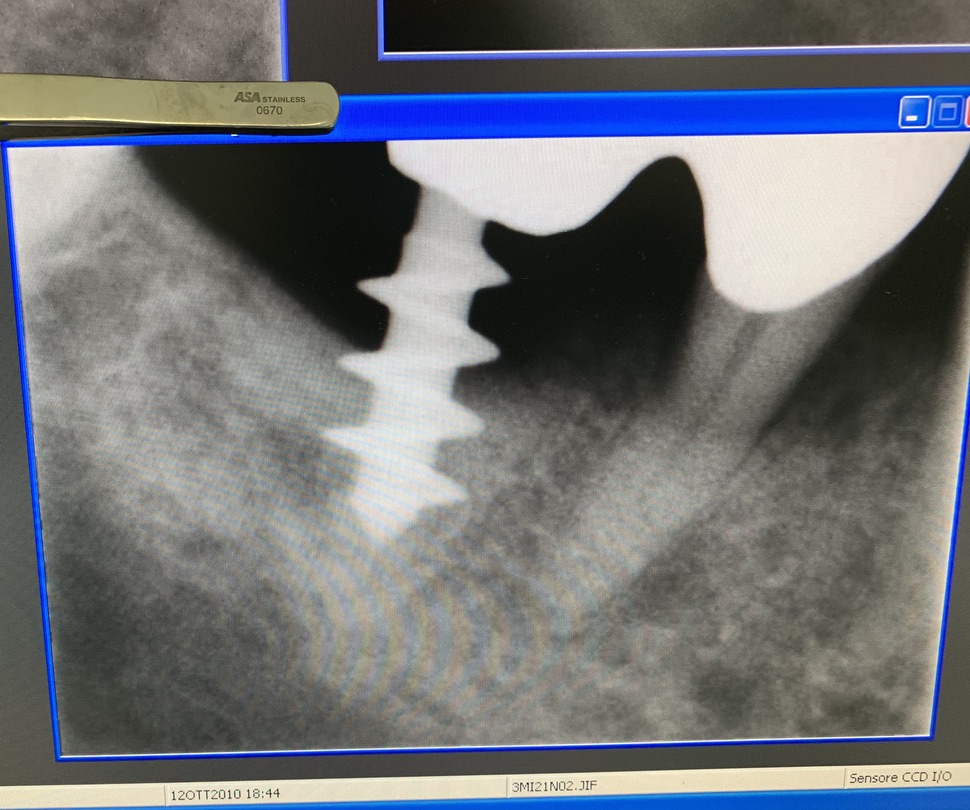

Forma originale dell’impianto di Tramonte. Diametro 5 mm a 3 spire. Gambo diam. 2,1 mm. Collo diam.2 mm x 5 mm di lunghezza. Titanio di grado 2. Il grado 2 consentiva al bisogno di piegare il collo dell’impianto per migliorare il parallelismo. Si tratta di un impianto postestrattivo immediato. Perciò nella stessa seduta estrazione, alesatura maschiatura ed inserimento dell’impianto. Subito seguiti da monconizzazione e da confezione di corone provvisorie in occlusione leggera. Le radiografie fornite evidenziano la situazione a partire dal 2010. La emergenza del collo sottile favorisce la formazione di un manicotto di gengiva densa che protegge dalle periimplantiti. Le spire larghe irradiano lontano dal corpo impianto il carico occlusale favorendo la formazione di un osso più omogeneo.